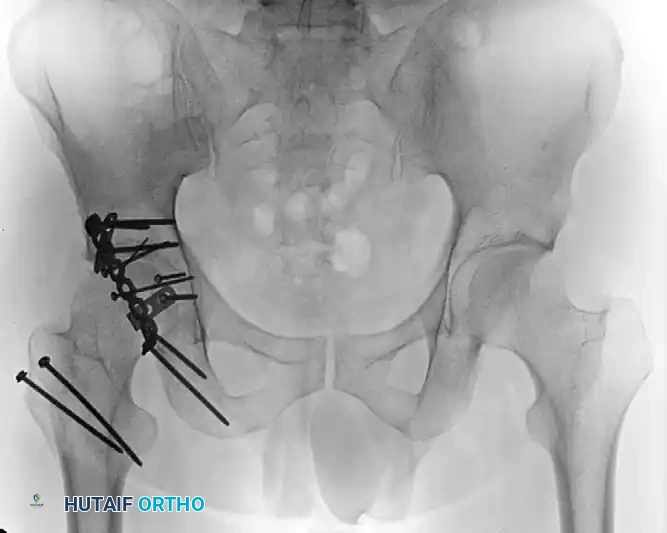

Figure 55-61E: Postoperative AP pelvic radiograph showing the final construct.